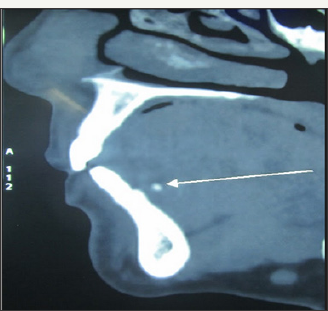

A 58 year old female reported with a chief complaint of intermittent swelling in left submandibular region. The swelling was related to meals and persisted for 2-3 hours after food. It was variable in size and occurrence. On examination, there was mild swelling in submandibular region (Figure 1). Ductal orifice was slightly reddish and tender signifying inflammation. Expressed saliva was normal in appearance and consistency but the salivary flow was relatively reduced compared to contra lateral side. Clinical diagnosis of left submandibular sialolith was made. A computerised tomogram revealed a 2.4mm radiopaque mass in anterior part of the left Wharton's duct (Figure 2a-2c). However, the calculus was not visible or palpable. The sialolith was removed intra orally under local anesthesia. The surgical technique has already been discussed (Figure 3-7).

Figure 2c: Sagittal section of CT showing sialolith.